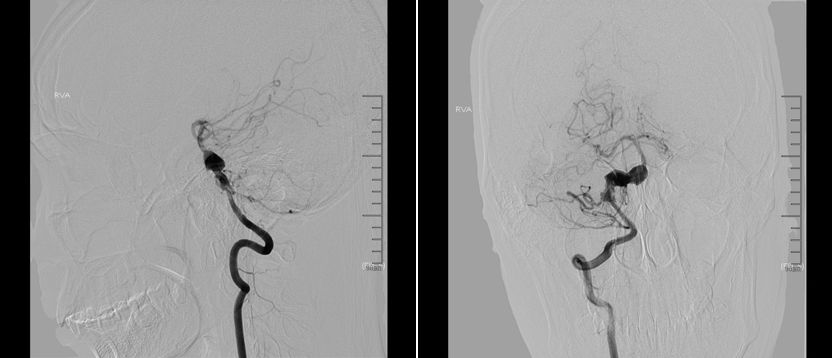

术中路途显示下Synchro-14 200微导丝携Mrksman微导管小心通过PED支架及基底动脉夹层动脉瘤,超选进入右侧大脑后动脉P2段。

PED支架顺利释放,与原支架顺利桥接重叠。术后即刻造影显示PED位置满意,动脉瘤内可见造影剂滞留。

DynaCT显示两枚支架形态良好。

术后1个月复查头颅CTA显示支架位置良好,左侧椎动脉与基底动脉汇合处闭塞,左侧小脑后下动脉动脉瘤仍显影。